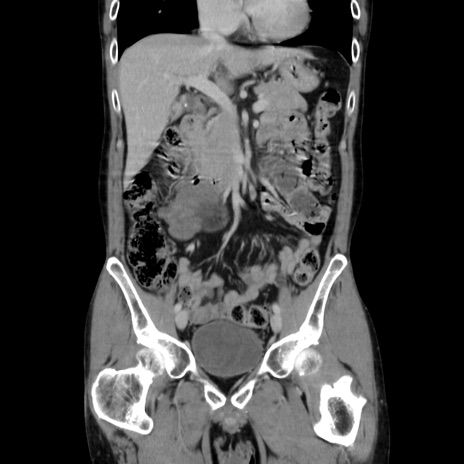

症例37(冠状断像)

【症例】40歳代 男性

【主訴】腹痛

【現病歴】4時間ほど前に電車に乗車中に臍部上より腹痛出現。徐々に増悪し起立困難となり、救急外来受診。生ものは数日食べていない。今朝お雑煮を食べた。

【身体所見】BT 36.8℃、BP 117/84mmHg、HR 91/min、SpO2 97%、苦悶様、腹部:臍上部広範囲圧痛あり、反跳痛±

【データ】WBC 8100、CRP 0.03